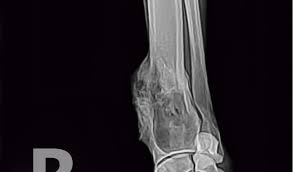

Signs Of Bone Cancer In Dogs Leg - Dr Wiltzius Shares Canine Bone Cancer Diagnosis Staging And What To Expect - Osteosarcoma is a word derived from osteo, meaning bone, and sarcoma, meaning cancer.. They can include swelling, lameness, and joint or bone pain. Veterinarians often use the phrase away from the elbows & toward the knees to remember the anatomically predisposed sites, including: Dog bone cancer warning signs sometimes bone cancer makes a sudden appearance as a lump in the leg, or in worst case scenario, as a pathologic fracture. When the tumor first appears, the site usually looks slightly swollen. Or a dramatic, sudden fracture.

Other types of bone cancer include chondrosarcoma, fibrosarcoma, and hemangiosarcoma. Osteosarcoma is a common dog cancer in large breeds, and it most often affects the long bones of the legs. Most dogs will show signs of swelling and soreness in limbs close to joints. Usually, osteosarcoma develops in the long bones of the front legs, though the rear legs, jaw, face. Symptoms of bone cancer in dogs: If you decide to proceed with amputation, you will admit your pet into the hospital either the day before or the morning of surgery. Canine bone cancer may be part of the diagnosis. Sometimes a biopsy is performed by taking a small piece of bone and testing it. They can include swelling, lameness, and joint or bone pain. The early signs of bone cancer in dogs can difficult for pet parents to recognize since symptoms tend to be subtle. Symptoms and types many signs of bone cancer are subtle. (most dogs with this kind of cancer do not survive beyond a year with amputation alone. Canine bone cancer symptoms osteosarcoma tumors typically form in a dog's long bones, or growth bones, and are found frequently below the elbow or near the knee or shoulder.

Dog bone cancer warning signs sometimes bone cancer makes a sudden appearance as a lump in the leg, or in worst case scenario, as a pathologic fracture. As the tumor continues to grow, the bone containing the tumor will expand. Washington ( circa) — osteosarcoma (osa) is one of the most common forms of bone cancer seen in veterinary patients. Osteosarcoma is a type of bone cancer. Other types of bone cancer include chondrosarcoma, fibrosarcoma, and hemangiosarcoma. Since we can't ask our dogs how they are feeling each day, it's important to understand the signs of a sick dog. How to help our mastiff with bone cancer. While tumors usually occur in the long bones of the limbs, osteosarcoma can affect any bone. It's the cancer of the bones. Osteosarcoma is the most common bone cancer in dogs. Symptoms of bone cancer in dogs: Osteosarcoma (osa) at the top of the list, osteosarcoma is the most prevalent type of bone cancer in dogs. Sometimes a biopsy is performed by taking a small piece of bone and testing it.

Osteosarcoma Bone Cancer In Dogs from www.aspcapetinsurance.com Sadly, the outlook for a dog with an osteosarcoma. While tumors usually occur in the long bones of the limbs, osteosarcoma can affect any bone. This bone cancer grows very quickly and frequently spreads to other areas of the body, especially lymph nodes, lungs and other bones. The total length of anesthesia time is usually three to four hours. Lameness caused by osteosarcoma is typically mild at the onset, but then progresses over time. Osteosarcomas are painful tumours that often first appear as hot, solid, tender swellings. Osteosarcoma is a type of bone cancer. Sometimes a biopsy is performed by taking a small piece of bone and testing it.